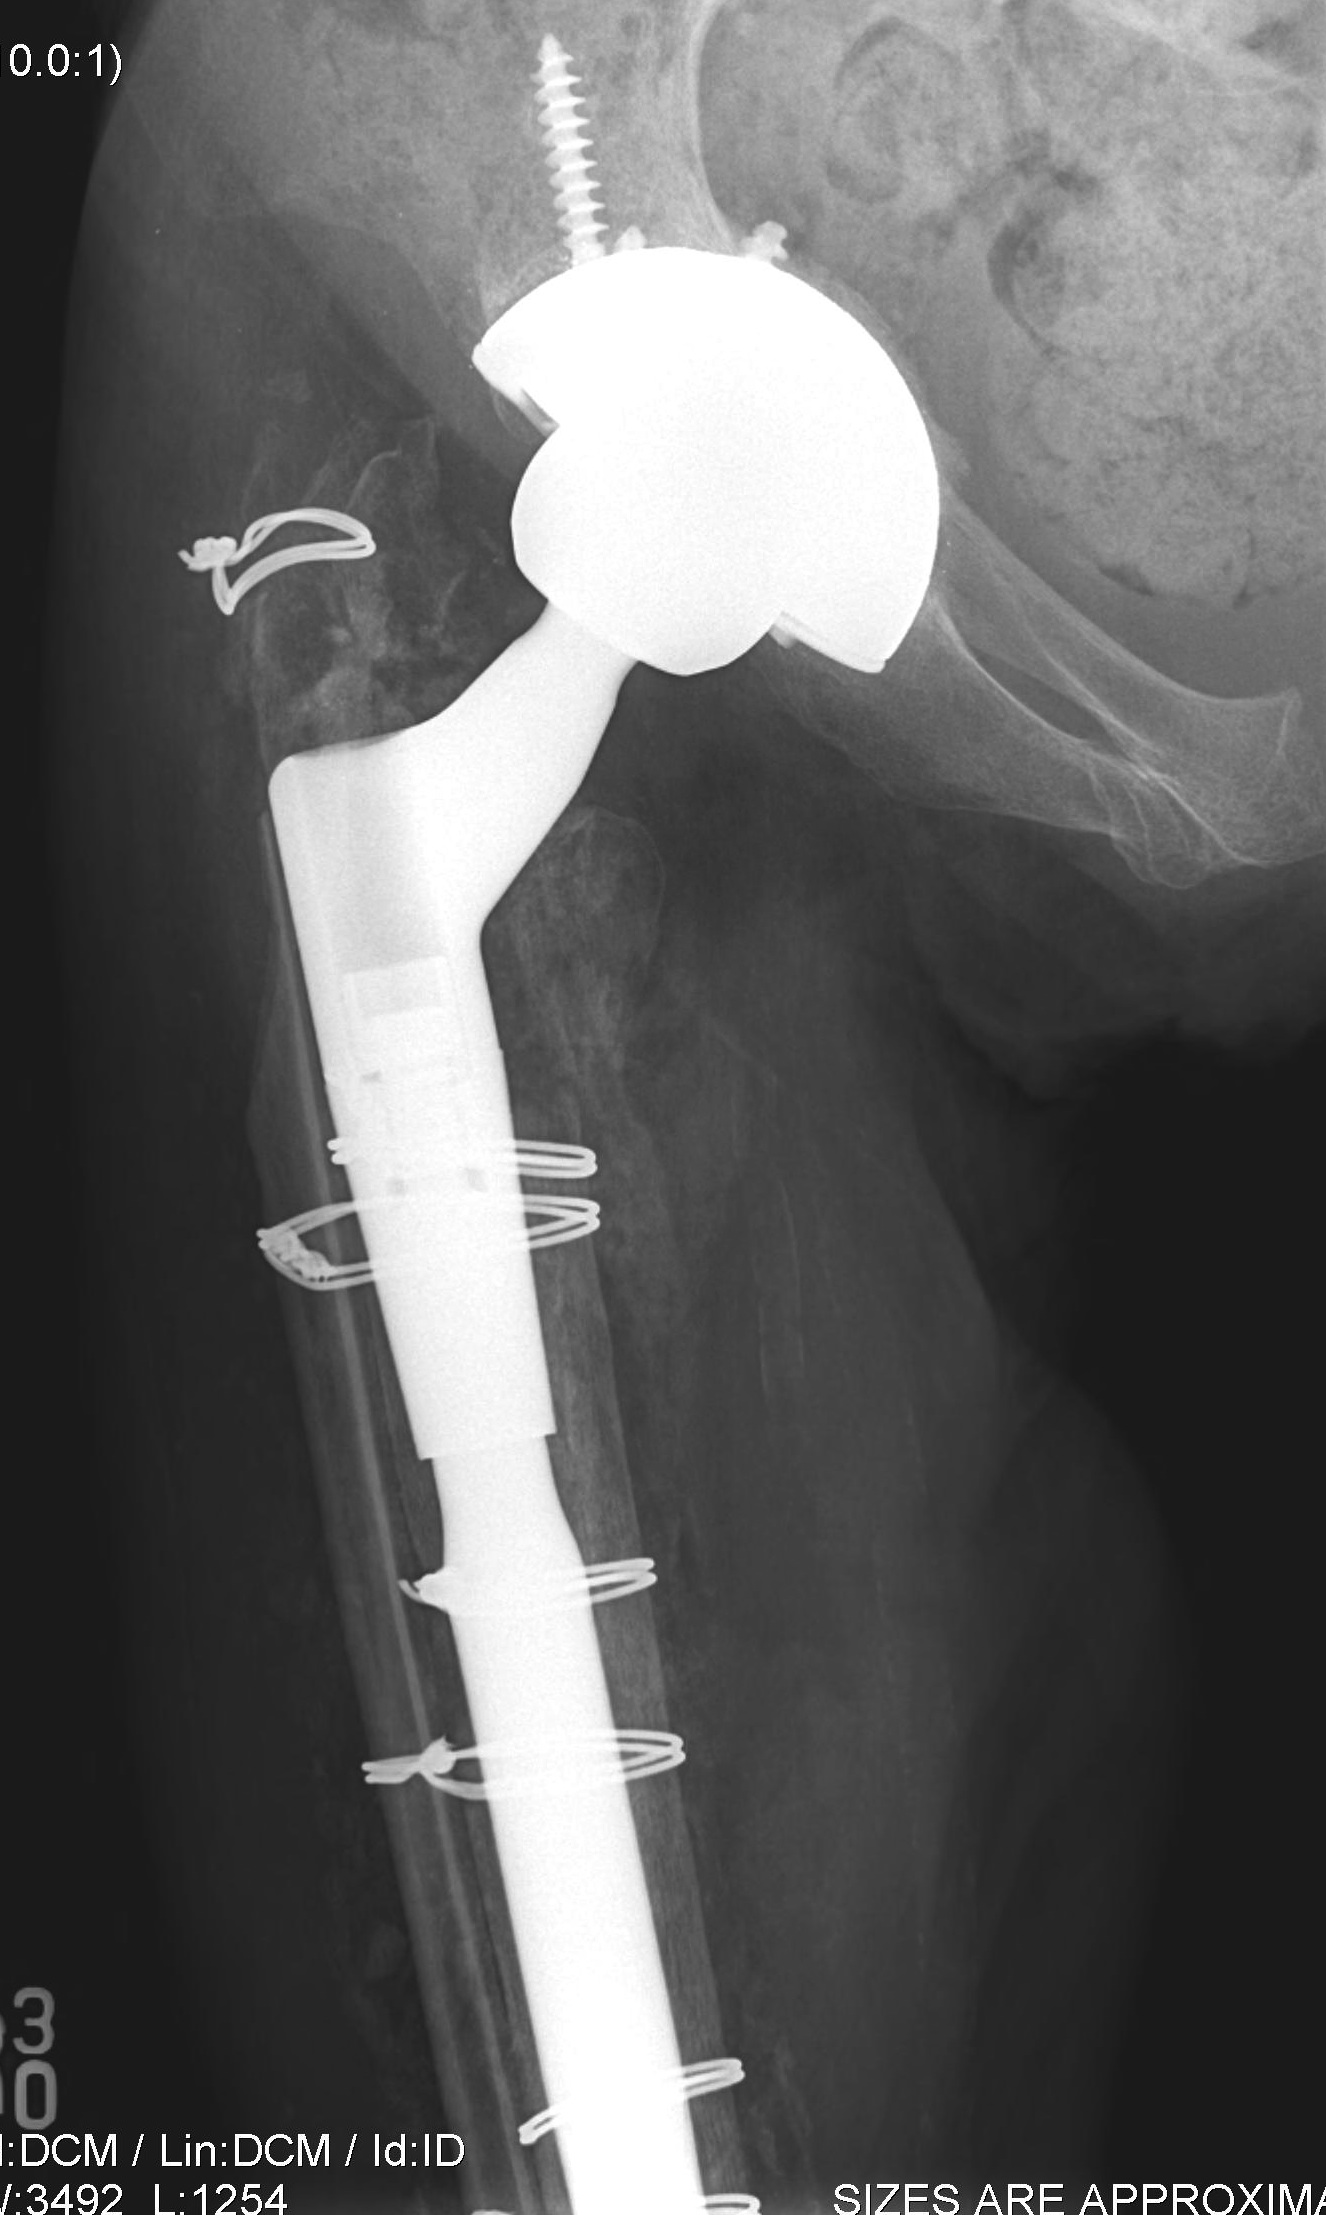

Revision uncemented arthroplasty with Zimmer cable plate

Long stem uncemented revision with cortical strut allograft

Long stem uncemented revision with plate + cortical struts